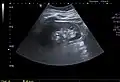

Renal ultrasonography of a simple renal cyst with posterior enhancement.